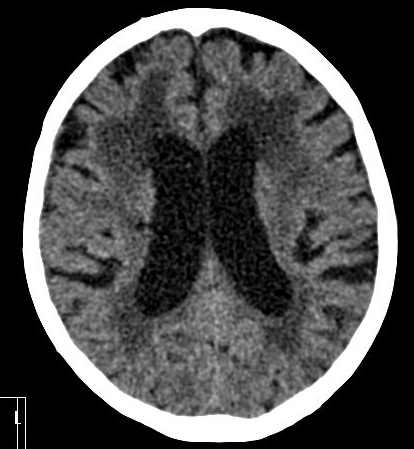

In acute phase (12-24 hours after the occlusion of the middle cerebral artery) on CT hypodense basal ganglia, the loss of cortical white-grey matter differentiation and sulcal effacement are the characteristic imaging findings.

In the chronic phase of the infarct (months to years) the hypodensity of the lesion (CT) reaches the level of the cerebrospinal fluid. There is no more contrast enhancement, the lesion is well differentiated and it degenerates into a cyst secondary to encephalomalacia. The brain parenchyma experiences a volume decrease due to the degeneration (sometimes calcifications can occur at the marginal border of the infarct).

On CT images acute bleeding always presents as hyperdensity. (One has to keep it mind that hyperdensity of the blood is affected by the hematocrit levels, hence making the diagnosis more difficult.) Intraparenchymal blood is dominated by a destructive appearance (mass-effect) and it is surrounded by hypodensity as a sign of perifocal edema. It often breaks into the ventricles. In patients lying in a supine position they collect (sediment) at the occipital horn of the lateral ventricles, creating a hyperdense liquid-to-liquid levels. Later on, the density of blood decreases and shows a peripheral ring or rim-like contrast enhancement without mass-effect.